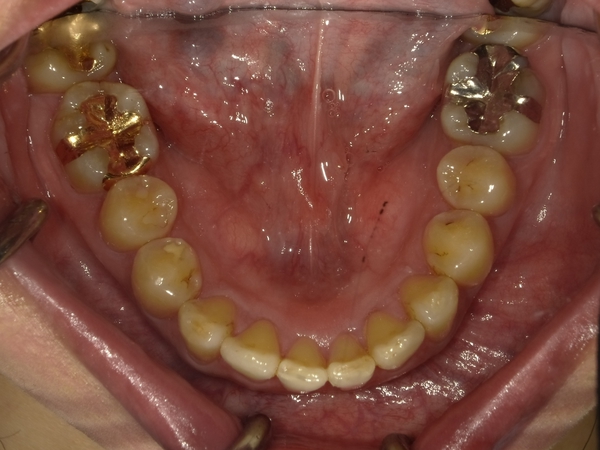

すきっぱ(空隙歯列)CASE4 2023.06.06 40代女性非抜歯BEFORE→AFTER〇ご相談内容:歯と歯の間があいている、下の歯のがたつき〇矯正の種類:マウスピース型矯正「インビザラインGO」〇治療期間:17週間〇治療費用:44万円(税込) < すきっぱ(空隙歯列)CASE5すきっ歯(空隙歯列弓)CASE3 > ブログ記事一覧をみる